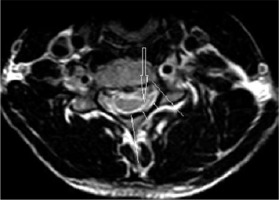

Figure 5

T2W sagittal section of cervical spine in the neutral position, in a 22-year-old patient showing hyperintensity in the cervical cord (solid arrow) and atrophy of the lower cervical cord (open small arrows)

Figure 6

T2W axial image of cervical spine at the C5 level, in the same patient with Hirayama disease showing asymmetrical cord atrophy more towards the right side with hyperintensity in the cord (arrow)

Altered intramedullary signal in the form of T2W hyper-intensity was seen in only 6 patients (35.2%) (Figures 5 and 6).

Another important imaging feature noted on flexion as well as neutral MRI is the lower cervical cord atrophy. This was seen in all the patients, with asymmetrical atrophy (82.3%) being much more common than symmetrical cord atrophy (17.6%). Similar findings of asymmetrical cord atrophy were also seen in other studies [1,10,13,23,27]. A “posterior epidural ligament factor” has been proposed by Shinomiya et al. [28] for this asymmetrical cord atrophy. These are the ligaments between the posterior dura mater and the ligamentum flavum, which prevent the separation of the posterior dura from the ligamentum flavum. These are abundant at the C1 and C2 levels and sparse at the C6 and C7 levels. An abnormally unequal distribution or lack of these ligaments at the lower cervical level may be the main cause of asymmetric cord compression. The extent of cord atrophy ranged from the C4 to the C7 level with involvement of the C5 and C6 level in all the patients in our study.

Hyperintense signal in the cervical cord on T2W images was seen in 35.2% of our patients, unlike the study by Hassan et al. in which it was seen in 18% of the patients with HD [29]. Intramedullary high signal intensity can be present because of more severe ischaemic change or gliosis in the vulnerable areas, but its incidence is lower than that of localized lower cervical cord atrophy [5,17].